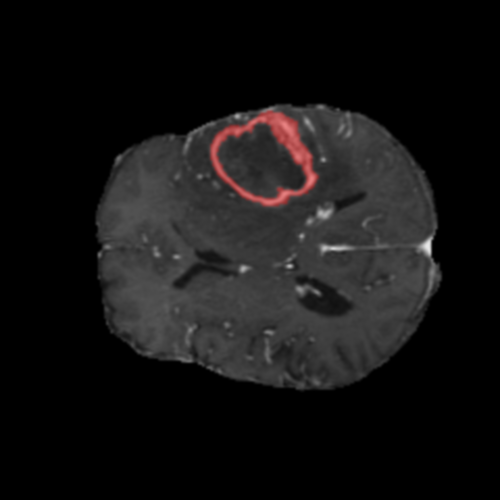

Ejemplos de Modalidades MRI

Visualización de las 4 modalidades de resonancia magnética y las segmentaciones de zonas tumorales utilizadas para entrenar el modelo

Glioma de Alto Grado (HGG)

Núcleo HGG

Núcleo

🎯 Zonas Tumorales Segmentadas

• Núcleo (NCR): Región central no viable y necrótica del tumor

• Edema (ED): Inflamación (acumulación de líquido) en tejido cerebral sano circundante

• Realce (ET): Parte activa y viable del tumor, identificada por captación del contraste en T1ce